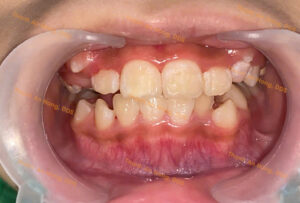

Sắp đều răng trong độ tuổi tăng trưởng với mắc cài